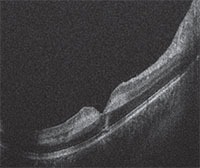

Because the patient could not sit for a desktop optical coherence tomography (OCT) test due to his injuries, we performed a handheld OCT that demonstrated no gross intraretinal or subretinal fluid but did show hyper-reflective intraretinal lesions (Figure 2). We deferred further workup given the strong clinical suspicion for fat embolism to the retinal microvasculature leading to a Purtscher-like retinopathy.

| Figure 2. Handheld optical coherence tomography imaging of the macula (right eye shown here) demonstrated foveal contour preservation with alteration of the normal retinal architecture. Imaging showed a hyper-reflective lesion of the inner nuclear and outer plexiform layers, but no gross intraretinal or subretinal fluid. |